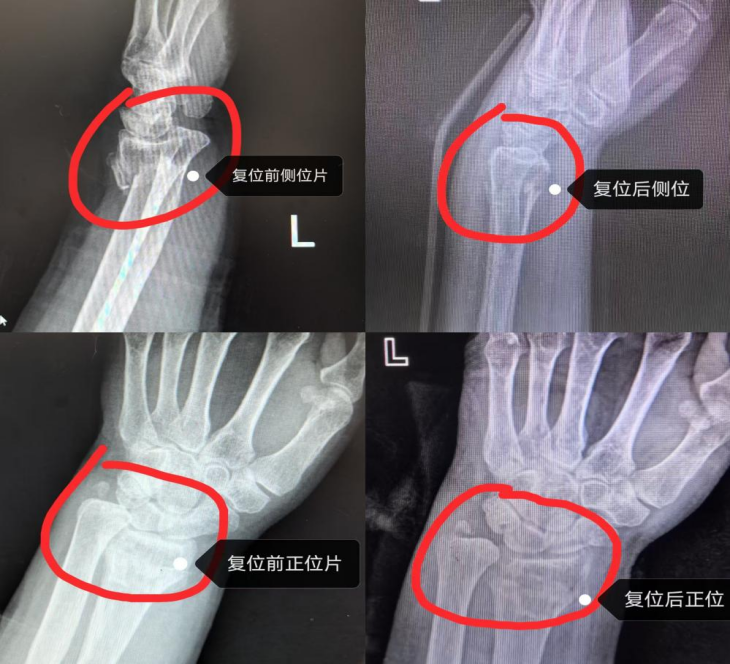

复位前后对比图

与家属充分沟通并获得其同意后,在科室主任熊明月的指导下,石辉辉为岳奶奶进行了手法复位治疗。只见他凝神聚力,双手精准拿捏骨折部位,凭借多年积累的临床经验和对骨骼解剖结构的精准把握,轻柔发力、巧妙调整。短短几分钟,石辉辉便轻声告知“复位好了”。岳奶奶半信半疑地活动了一下手腕,原本剧烈的疼痛感竟已明显减轻,脸上的愁容瞬间舒展。后续复查的影像清晰显示,此前移位的骨骼已精准复位至正常位置,复位效果堪称“近乎完美”,完全无需进行手术治疗,岳奶奶和家人不由得为这份精湛医术连连点赞。